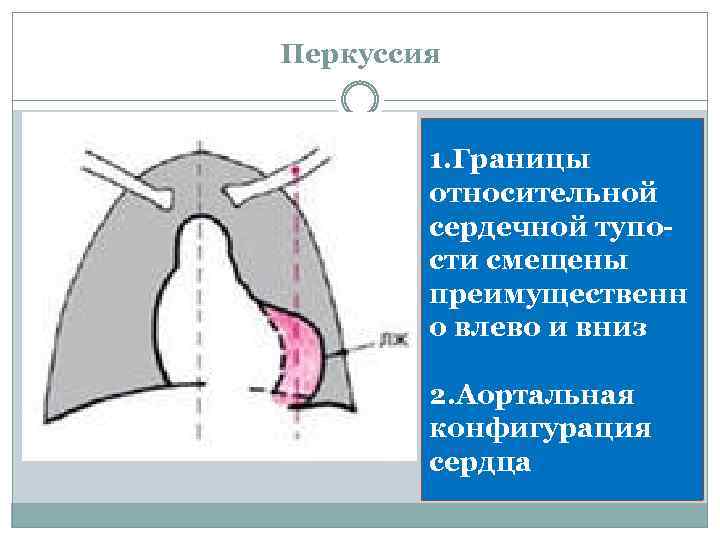

Перкуссия 1. Границы относительной сердечной тупости смещены преимущественн о влево и вниз 2. Аортальная конфигурация сердца